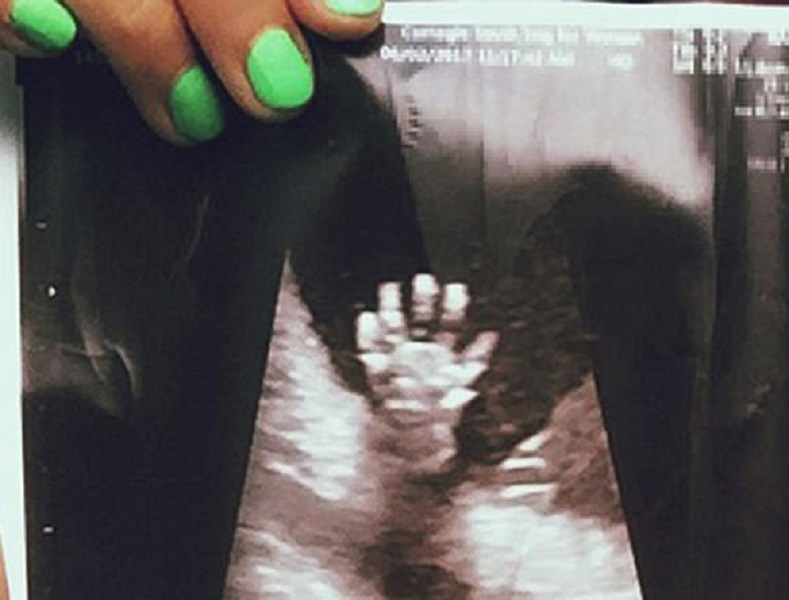

NEW YORK – Una coppia di genitori in attesa del loro secondo figlio sono rimasti sorpresi quando hanno visto la scansione della radiografia fatta alla mamma, alla ventesima settimana di parto. All’interno del grembo materno, il piccolo nato sembra dare loro il “cinque”. Libby e Mathew Vlasic di New York sono rimasti colpiti e soprattutto felicissimi di sapere che Miles, il loro figlio di sei anni, avrà una sorellina che sta crescendo proprio bene. Lo dimostra anche la foto che i genitori hanno deciso di condividere facendola diventare virale in poco tempo.

La scansione è stata fatta alla ventesima settimana. La coppia è rimasta favorevolmente sorpresa nel vedere la piccola che dà il “cinque”. Libby, al Daily Mail ha raccontato: “Ci sono voluti parecchi anni di tentativi per avere un secondo figlio. E’ stata una lotta. Avevo abbandonato molto la speranza di avere un secondo bambino, ma la vita lavora in modi misteriosi e mi sono miracolosamente trovata di nuovo incinta. Nel giorno della scansione, non mi sentivo molto bene fisicamente, quindi mi ci sono voluti un po ‘di minuti per capire cosa stesse successo. Poi, il tecnico di scansione era molto entusiasta di quello che aveva visto a livello medico. Mi ha consegnato la foto e mi sono resa conto di quanto fosse speciale la mia bambina”.

Libby, che ora ha 30 settimane di gravidanza, ha raccontato di aver condiviso la foto su profili dedicati, su Instagram, proprio alla gravidanza, scoprendo che, in pochi giorni aveva superato le 6000 condivisioni.